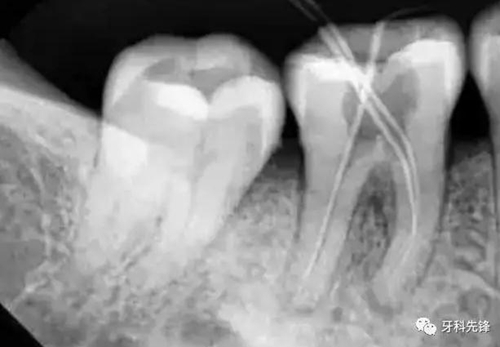

3、確定根管工作長度

應(yīng)用平行投照X線方法、根管長度測量儀確定根管度,最好插針拍X片。